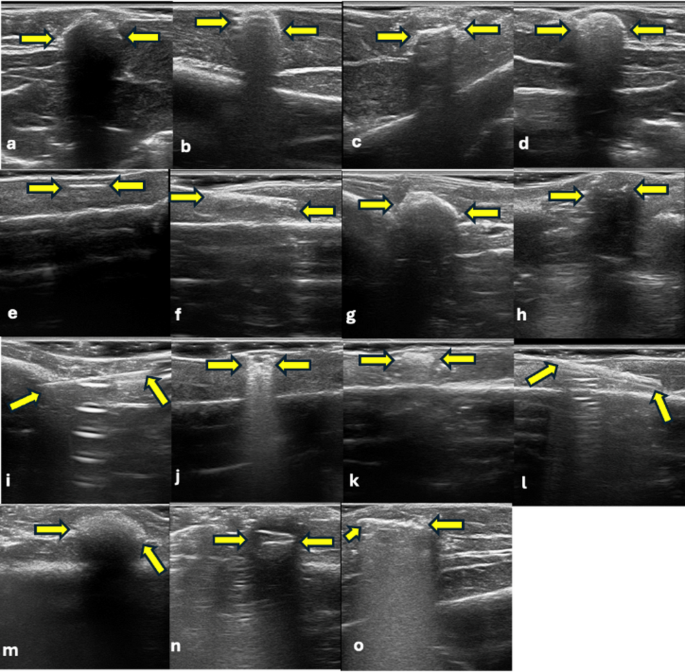

Ultrasonographic visualization of DMs; (a) Composite, (b) Amalgam, (c) Glass-ionomer cement, (d) Zinc polycarboxylate cement, (e) Gutta percha, (f) Paper point, (g) Cold-curing acrylic, (h) Dental pink wax, (i) Injector needle, (j) Stainless steel bracket, (k) Ceramic bracket, (l) Ni-Ti wires, (m) Alginate, (n) Acrylic tooth, and (o) Metal ceramic crown.

Table 4 presents detailed information on the CBCT visibility and radiopacity, as well as USG visibility, echogenicity, and artifact presence for each DM. In CBCT, paper point and wax were not visible, whereas all materials were detected with USG. In CBCT, acrylic, ceramic bracket, alginate, and acrylic tooth were classified as “slightly opaque.” In USG, most materials appeared hyperechoic, with alginate being the only material identified as isoechoic. Artifact patterns varied depending on the material, with posterior acoustic shadowing and comet-tail artifacts being the most frequently observed. This table clearly shows the differences in performance and imaging characteristics between the two modalities based on material type (Figs. 2 and 3).

The detection performance of imaging modalities depends on the physical principles underlying the technology used. In CBCT, visibility is determined by a material’s ability to attenuate X-rays, known as radiopacity, and the difference in density between the material and the surrounding tissue. Due to their high X-ray attenuation, materials containing metal (e.g., amalgam, metal-ceramic crowns, and Ni-Ti wires) are clearly visualized. In contrast, low-density organic materials, such as paper point and wax, were not detectable on CBCT due to their low X-ray absorption. Visibility in USG depends on the difference in acoustic impedance between the material and the surrounding tissue. A high impedance mismatch results in a strong reflection of ultrasound waves, producing a hyperechoic appearance6,9,10,16. In our study, most materials appeared hyperechoic, whereas alginate, which has a density close to water, was evaluated as isoechoic. This can be attributed to the acoustic properties of alginate being similar to those of the surrounding soft tissue.

Artifacts can significantly impact the diagnostic accuracy of imaging methods. In CBCT, the most common artifacts are beam hardening, streaking, and scattering. High-density metal-containing materials (e.g., amalgam, metal-ceramic crowns, and Ni-Ti wires) strongly attenuate X-rays. This causes beam hardening, resulting in gray tone loss, reduced contrast, and masking of surrounding details. Streak artifacts are often seen around thin metallic structures and may obscure low-density or small foreign bodies within the shadow of metal artifacts. This can lead to false negatives. In USG, artifacts such as posterior acoustic shadowing and comet-tail patterns can assist in detecting foreign bodies, but they can also mislead interpretation. Shadowing is pronounced in materials with high acoustic impedance differences, while the comet-tail artifacts are typically observed around metallic materials. However, these findings may be faint or absent in small or low-reflectivity objects, and normal structures, such as calcifications or fibrotic tissue, can mimic them. Furthermore, prior surgical intervention may cause air to accumulate within the tissue, which complicates the imaging process and can result in erroneous findings. Accurate interpretation requires considering the physical properties of the material, the surrounding tissue, and the device settings. MAR algorithms in CBCT and multiplanar probe positioning in USG can improve diagnostic accuracy5,9,12,14,16,17.